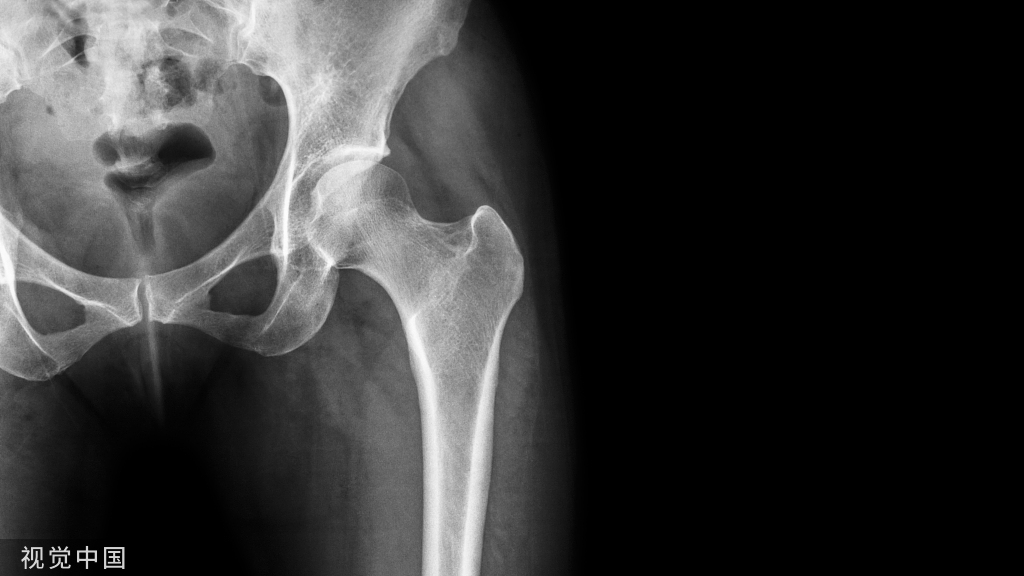

髋关节:前后位X线成像

髋部X线成像、髋关节成像与MRI